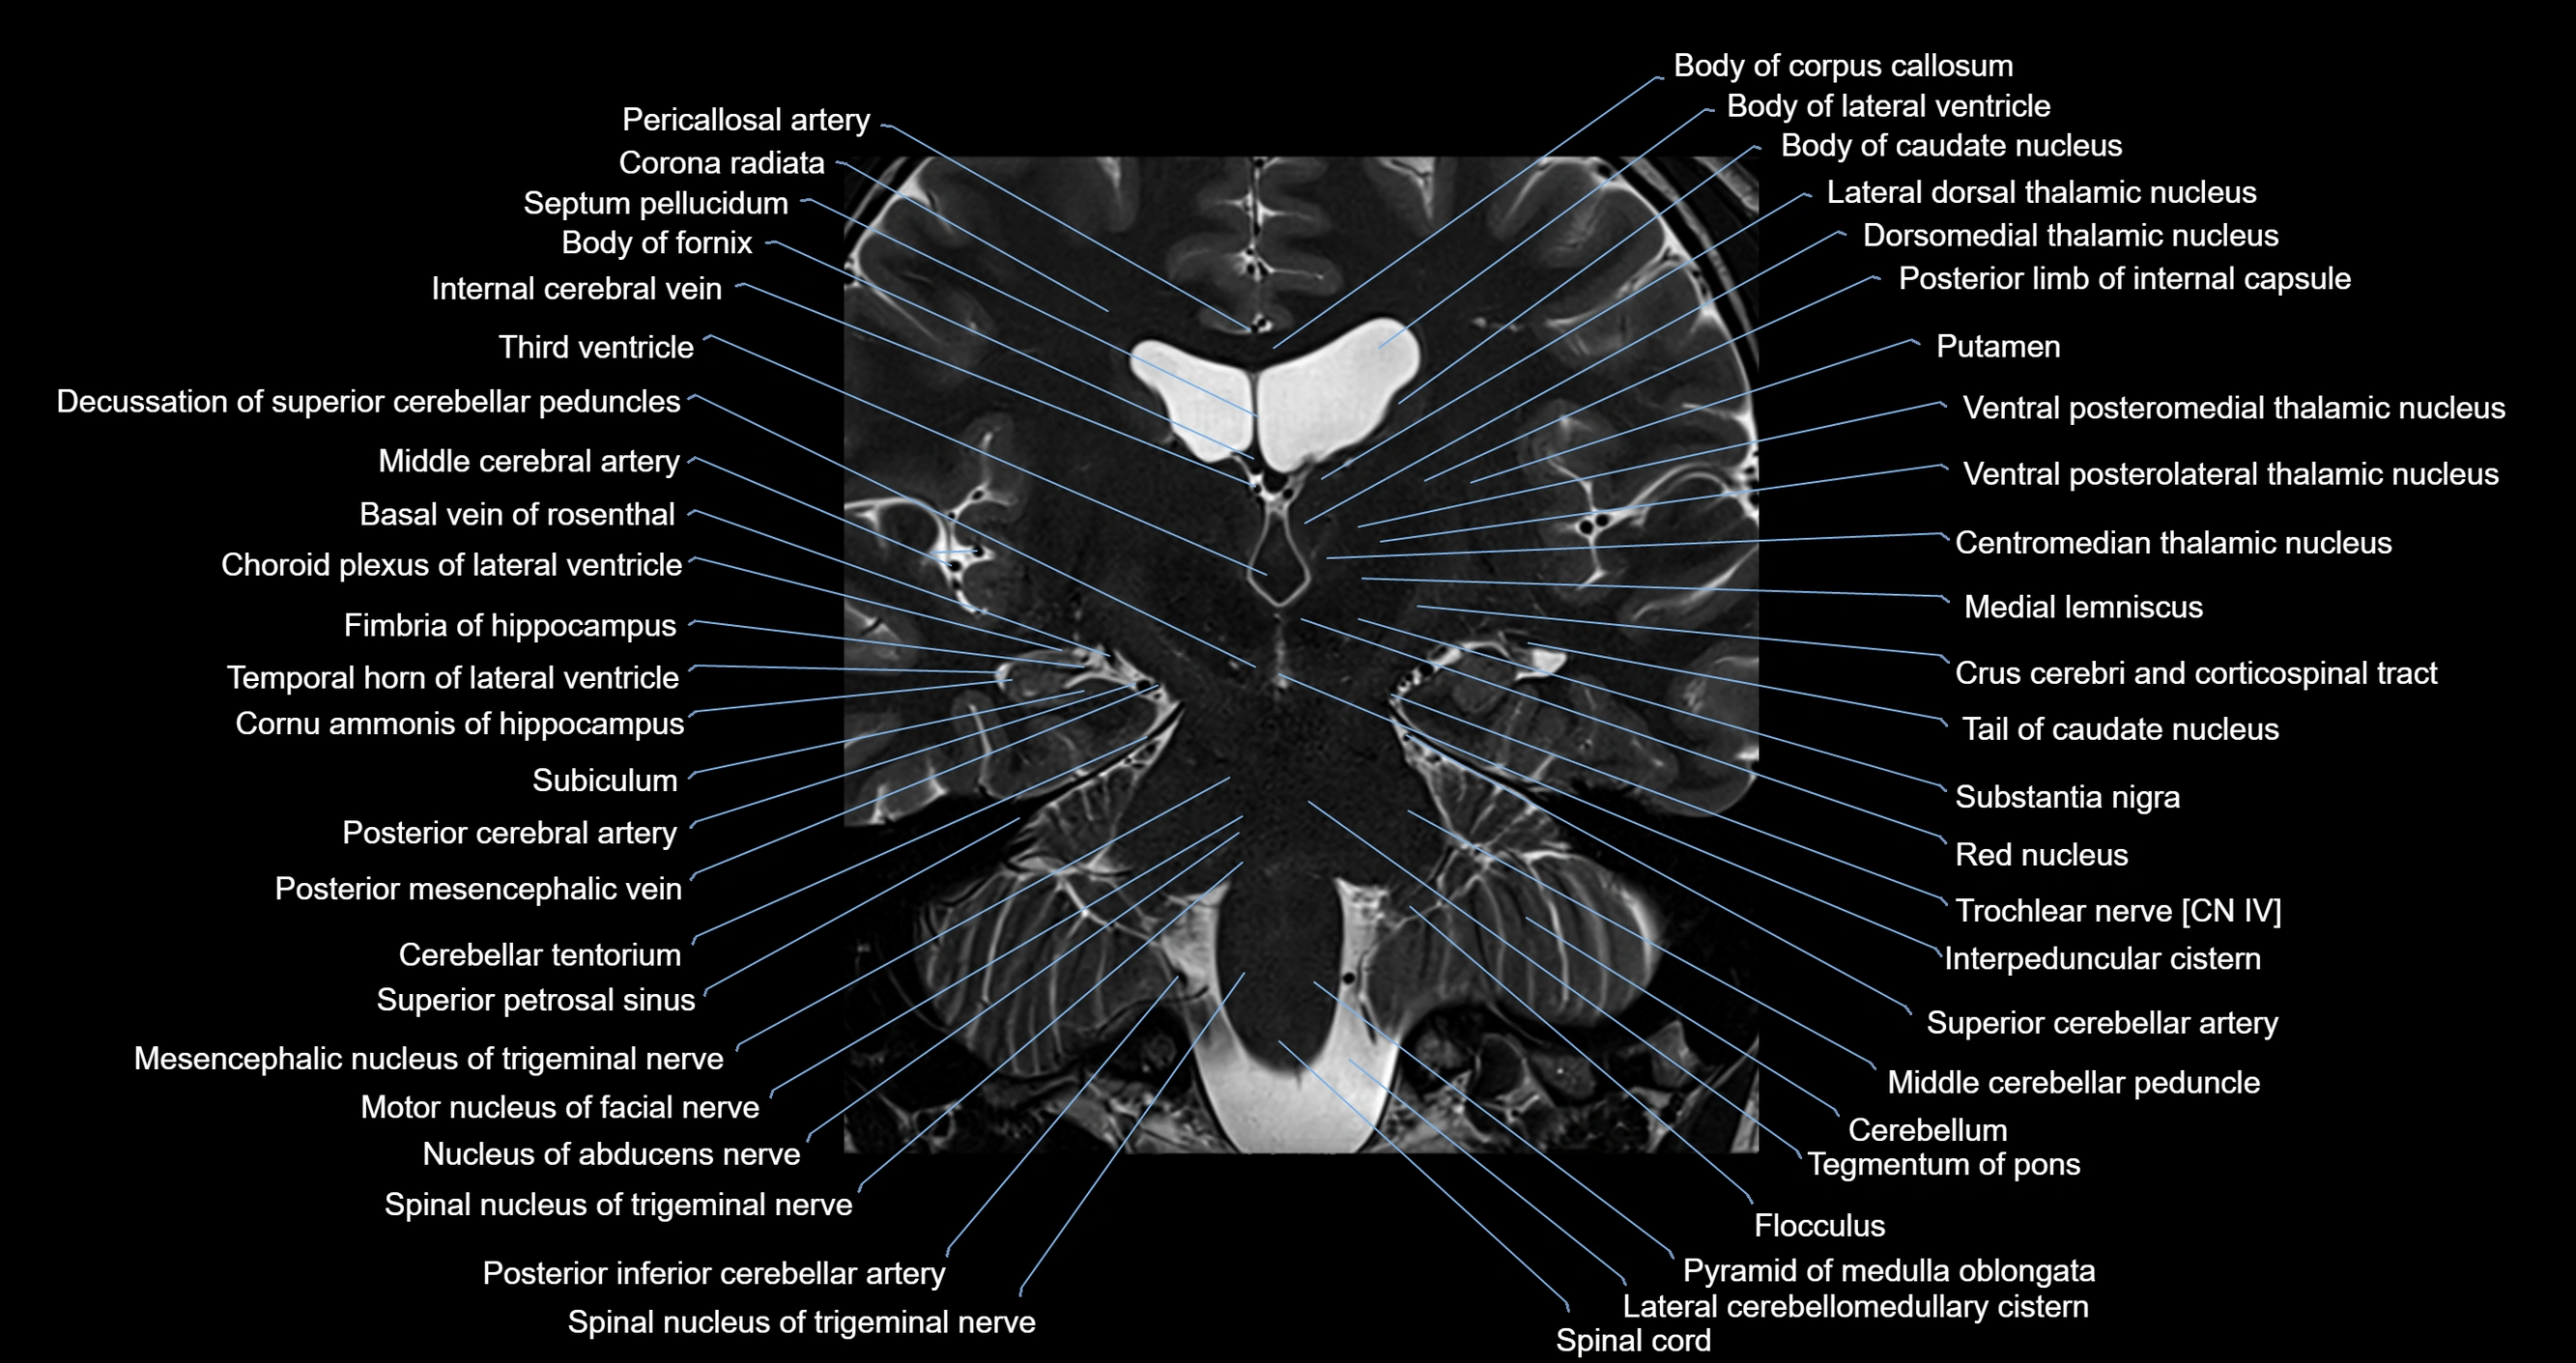

MRI images